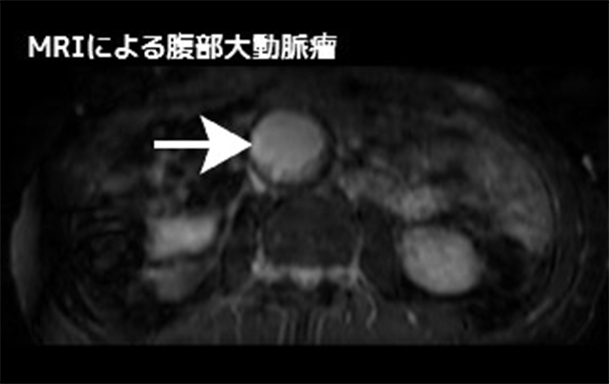

腹部大動脈瘤(Abdominal Aortic Aneurysm:AAA)

腹部大動脈の直径は個人差はありますが通常20mm前後です。

これが種々の原因によって動脈硬化が進行し、瘤化(風船の様に膨らんだ状態)したものを腹部大動脈瘤と呼びます。大部分が無症状であり、偶然発見されることが多いです。破裂したり、破裂直前になると症状(腹部や腰部の激痛)が出現し、緊急手術となります。当科では大動脈瘤・大動脈解離診療ガイドライン(日本循環器学会作成)に従い腹部大動脈瘤の手術適応の大きさは50mm(5cm)以上としておりますが、瘤の性状などを考慮してそれ以下の大きさで行う場合もあります。

当科では造影剤使用による腎機能障害の危険性を減らすため腹部大動脈ステントグラフト内挿術を行う際には以下の工夫を行うことで手術前後での腎機能の悪化を防止しております。

• 術前・術後検査にMRIやエコーの利用

• 血管内超音波の併用